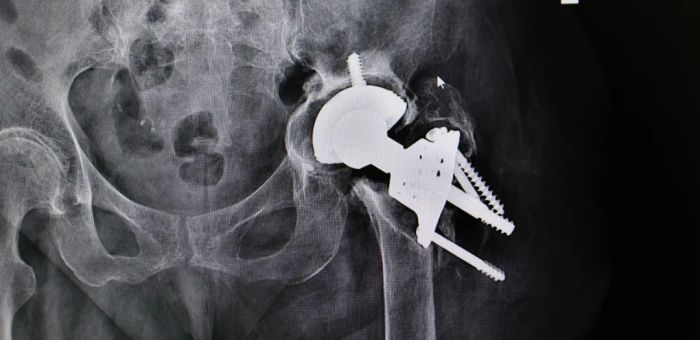

患者韦奶奶术前影像检查结果

然而患者的检查结果并不乐观,CT影像显示其原本置换的人工关节假体(左髋关节)松动,加之患者高龄伴随的严重骨质疏松,关节状况堪忧。此外,患者还因消化道出血而饱受贫血、便秘等困扰,营养状况较差,一系列因素使得手术治疗面临极大挑战。